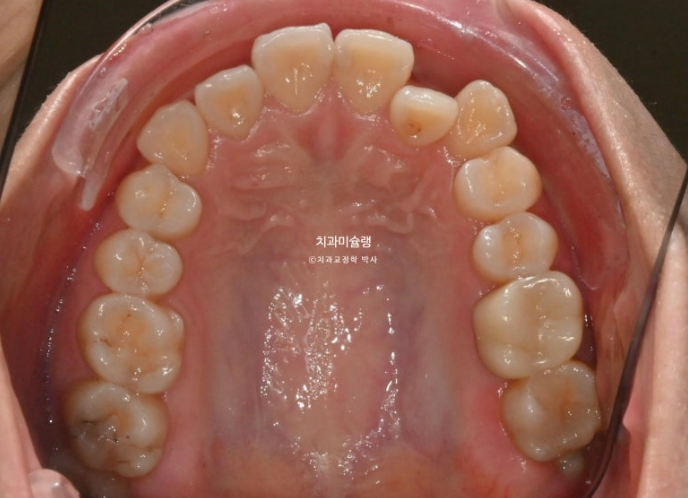

치간삭제를 하면 치아가 너무 작아지지 않으냐는 질문을 많이 받습니다.

또 시리지는 않을까 걱정하시죠.

25.03~25.12

이 사진에서 보듯 치아가 초진에 비해 작아질 정도까지 치간삭제를 하지는 않습니다.

만약 치아가 작아보일 정도까지 했거나 치아가 시려질때 까지 했다면 그건 치간삭제를 너무 과하게 한거죠.

통상 에나멜층에 한정해서 부위당 0.2mm씩 최소량 시행하면 치료에 도움이 됩니다.

그러나 그 양이 과하면 치아건강을 해지게 되겠죠.